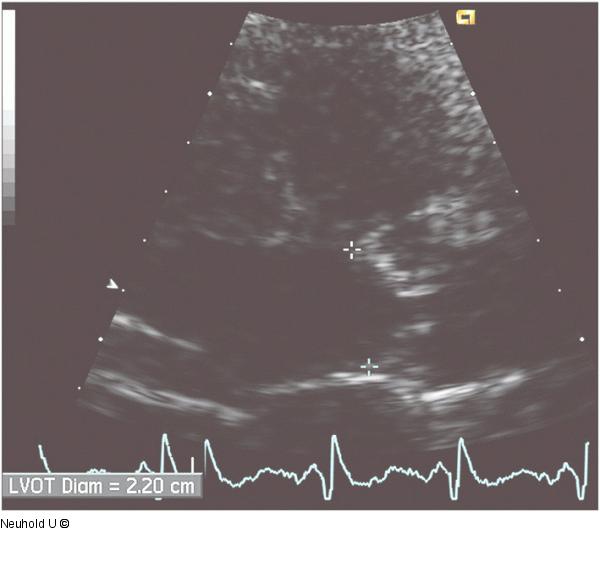

Abbildung 3: LVOT-Diameter Messung des LVOT-Diameters mesosystolisch (inner edge to inner edge) |

Messung des LVOT-Diameters mesosystolisch (inner edge to inner edge) |